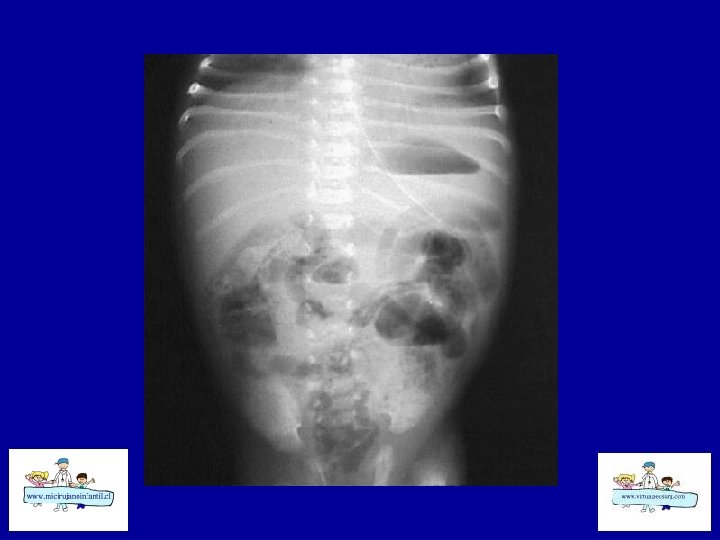

ECN-RADIOLOGÍA SIMPLE • • Distensión de asas Pneumatosis intestinal Asa fija (centinela) Gas Porta Edema de pared Ascitis Aire libre

ECN- CLASIFICACION (Bell) Etapa I: sospecha a CEG, sepsis inicial, Rx. distensión de asas moderada Etapa II: confirmada Ileo, sepsis más intensa , Rx: Ileo – pneumatosis b Hematoquezia Celulitis de pared, masa, grave, Rx: ascitis, gas porta Etapa III: grave Muy grave, CID, peritonitis Rx: ascitis Rx : pneumope ritoneo